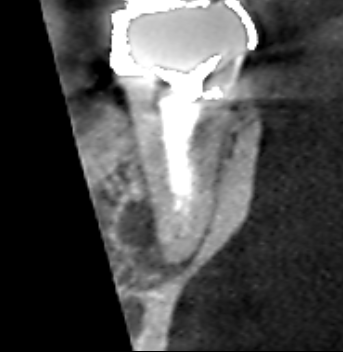

下顎第二大臼歯の冠状断のCT画像です。

矢印の先に膿の影がみられます。膿は根の舌側寄りに拡がっていました。レントゲンでは、根に隠れて膿の本体が把握しにくいケースです。